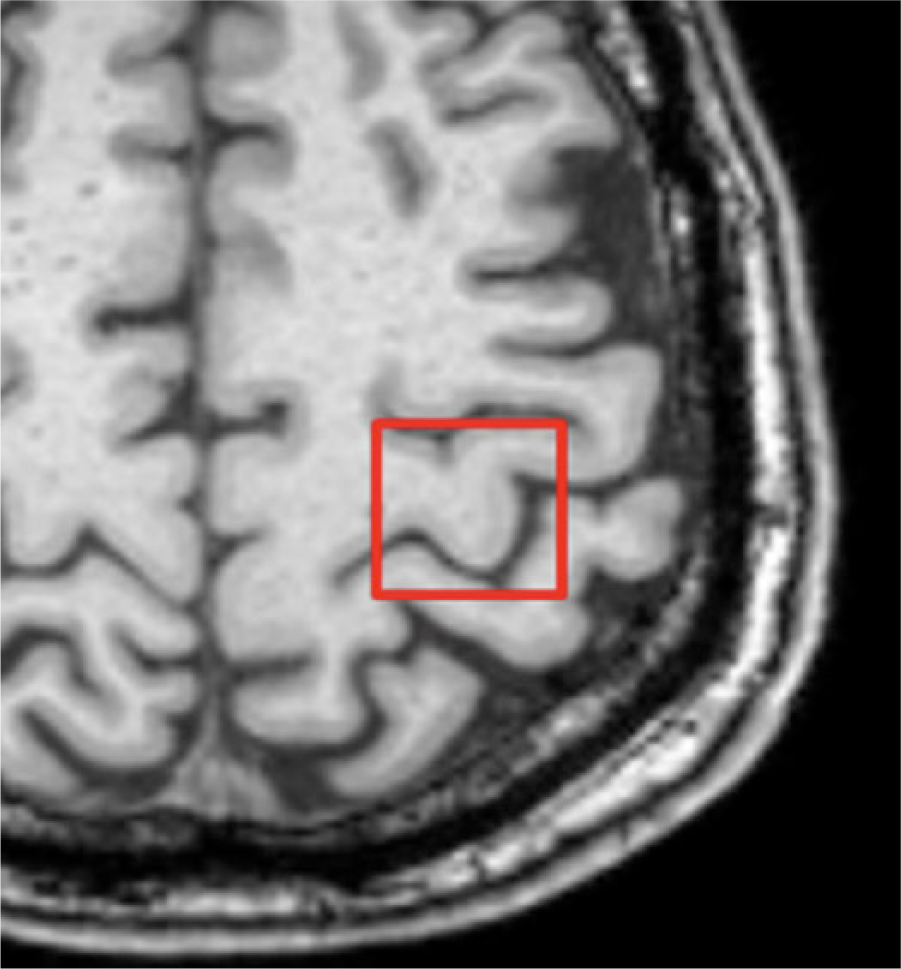

Participants were scanned on a 3T MR system (Siemens Trio, Erlangen, Germany). Patients were scanned before (mean 4 days) and after (mean 3 days) the 2 weeks of training, whereas healthy subjects were scanned only once. The scan protocol included structural T1 (MPRAGE), GABA-edited MRS, BOLD (blood oxygen level–dependent) functional and resting-state MRI with a total scan time close to 1 hour. The results from the functional and resting-state data will be published separately. A T1 MPRAGE scan (TR/TE 2420/3.7 ms, 1 mm isotropic resolution, scan time 5.5 minutes) was performed and used for voxel placement and post hoc tissue segmentation. GABA-edited MRS was performed using MEGA-PRESS (TR/TE = 2500/68 ms). Editing was achieved with a 14-ms dual-banded Gaussian editing pulse with 1 inversion band alternating between 1.9 ppm (edit-on) and 7.5 ppm (edit-off) in even and odd acquisitions, respectively, and a water suppression band centered at 4.7 ppm. A 2 × 2 × 2 cm voxel was placed in the “hand knob” area 19 of the affected hemisphere of the patients (Figure 1) and in the dominant hemisphere of the healthy subjects. A total of 186 averages each of edit-on and edit-off spectra were recorded leading to a scan time of 15.5 minute for MRS. A water reference scan was also acquired using 8 averages without an editing pulse.

Example of magnetic resonance spectroscopy voxel placement in the affected hemisphere.